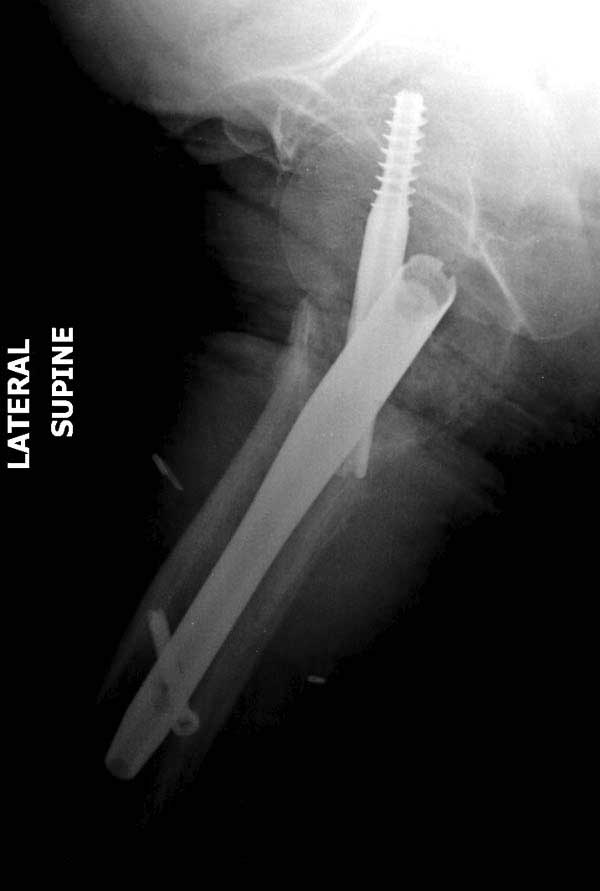

Такие “чужие осложнения” встречаются у всех и представляю банальный случай, который шаг за шагом показано как перерос в более сложный процесс... Больная 70 лет, множественные ко-морбидности, чрезвертельный перелом первоначально фиксирован Гамма 3. Осложнение в течение 6 недель, ревизия тотальной артропластикой и во время установки ножки обнаружена трещина диафиза (17), из малого доступа фиксация алло-графтом.

Повторно поступает после двух с половиной лет, где обнаруживается перелом на второй стороне. Немного сложно, но для фиксации выбрали Antegrade InterTan Smith Nephew Nail и с момента фиксации более 3х мес.